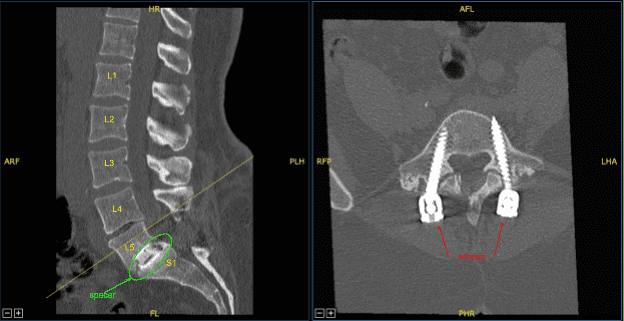

A continuación, se obtuvo un nuevo TAC, que mostró la posición correcta de los nuevos tornillos pediculares y del separador intercarrocés. Los procesos transversales bilaterales de L4, L5 y ala lateral fueron decorizados para la artrodesis. Las varillas precortadas y pre-contorneadas se reflejaban y colocaban sobre los tulipanes desde L4 hasta S1, se aseguraban con tapones de bloqueo y finalmente se apretaban con el dispositivo de par y antitorque.